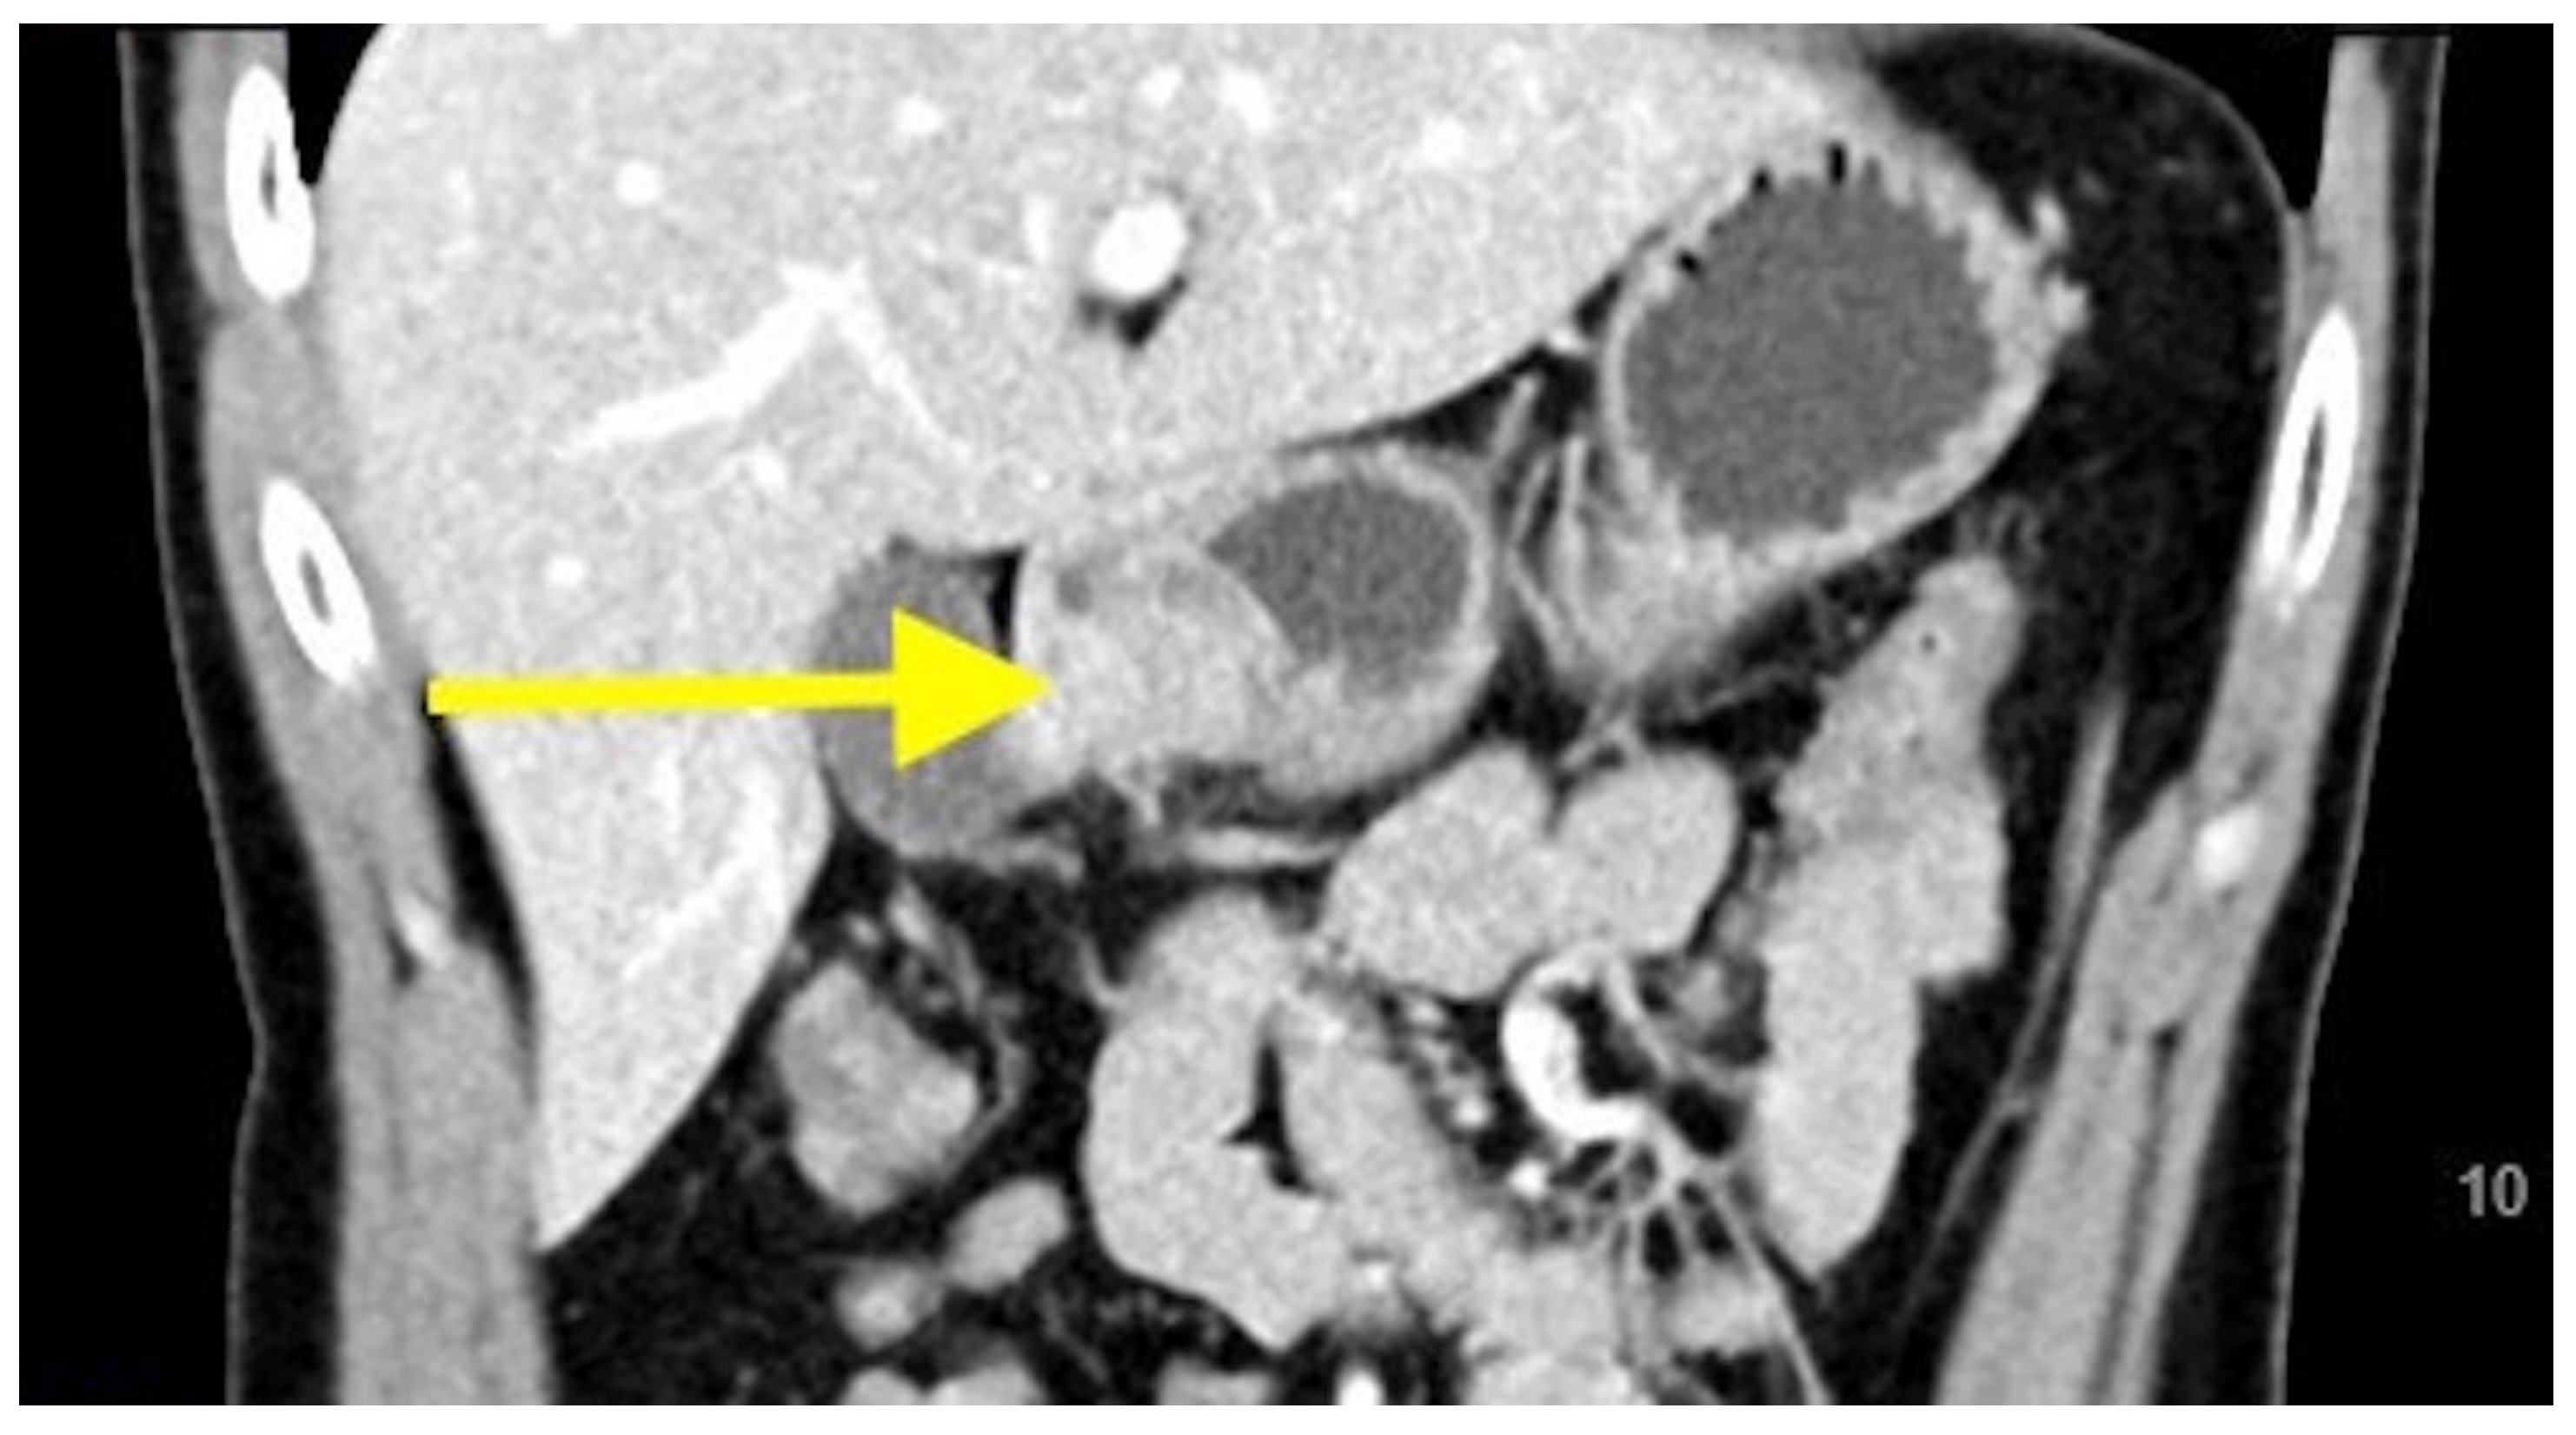

2. Case Report